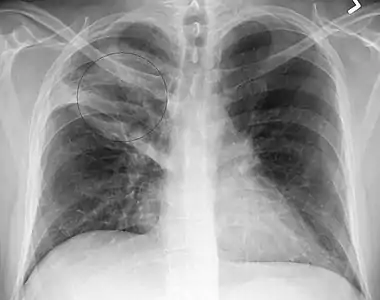

Right upper lobe pneumonia as marked by the circle.